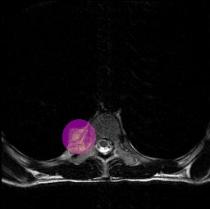

MRI Spine

The MHE Research Foundation's X-Ray & Image Gallery

These X-rays & Images were obtained from a variety of children with MHE / MO / HME